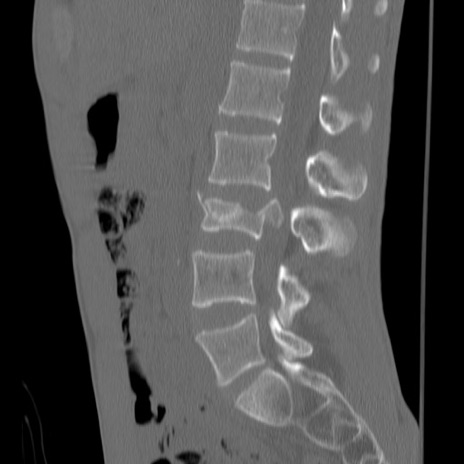

症例3 腰椎CT(矢状断像)

【症例】30歳代男性

【主訴】腰痛

【現病歴】本日旅行先で観光中に、友人と衝突し転倒し受傷。

【身体所見】麻痺なし、右下腿内側前面外側、左下腿内側に知覚鈍麻・しびれ

異常所見と診断は?

腰椎CT